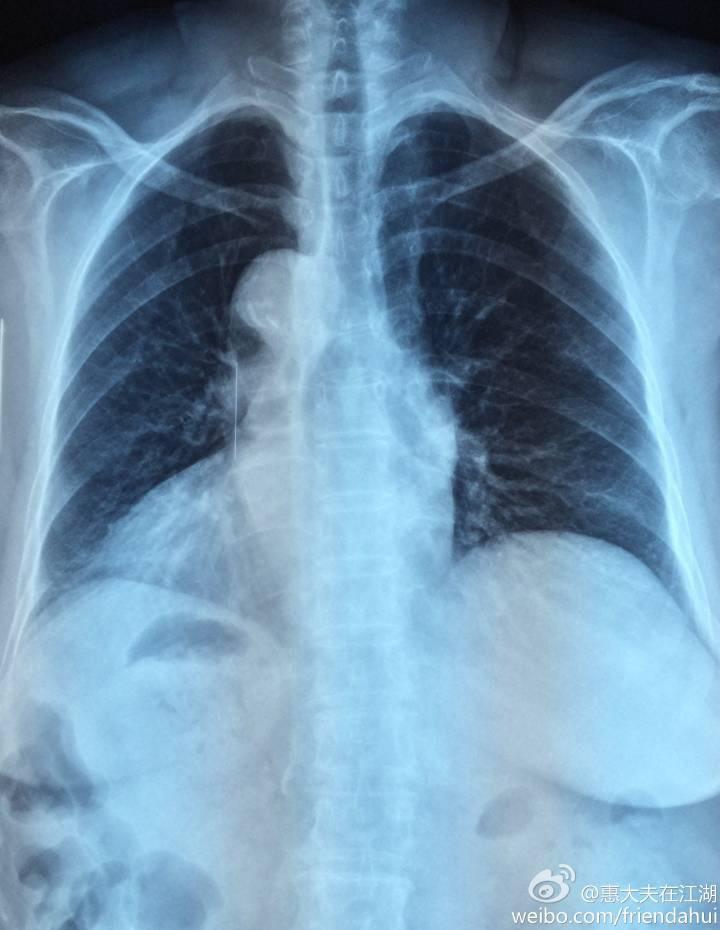

右位心胸片

右位心胸片,

右位心